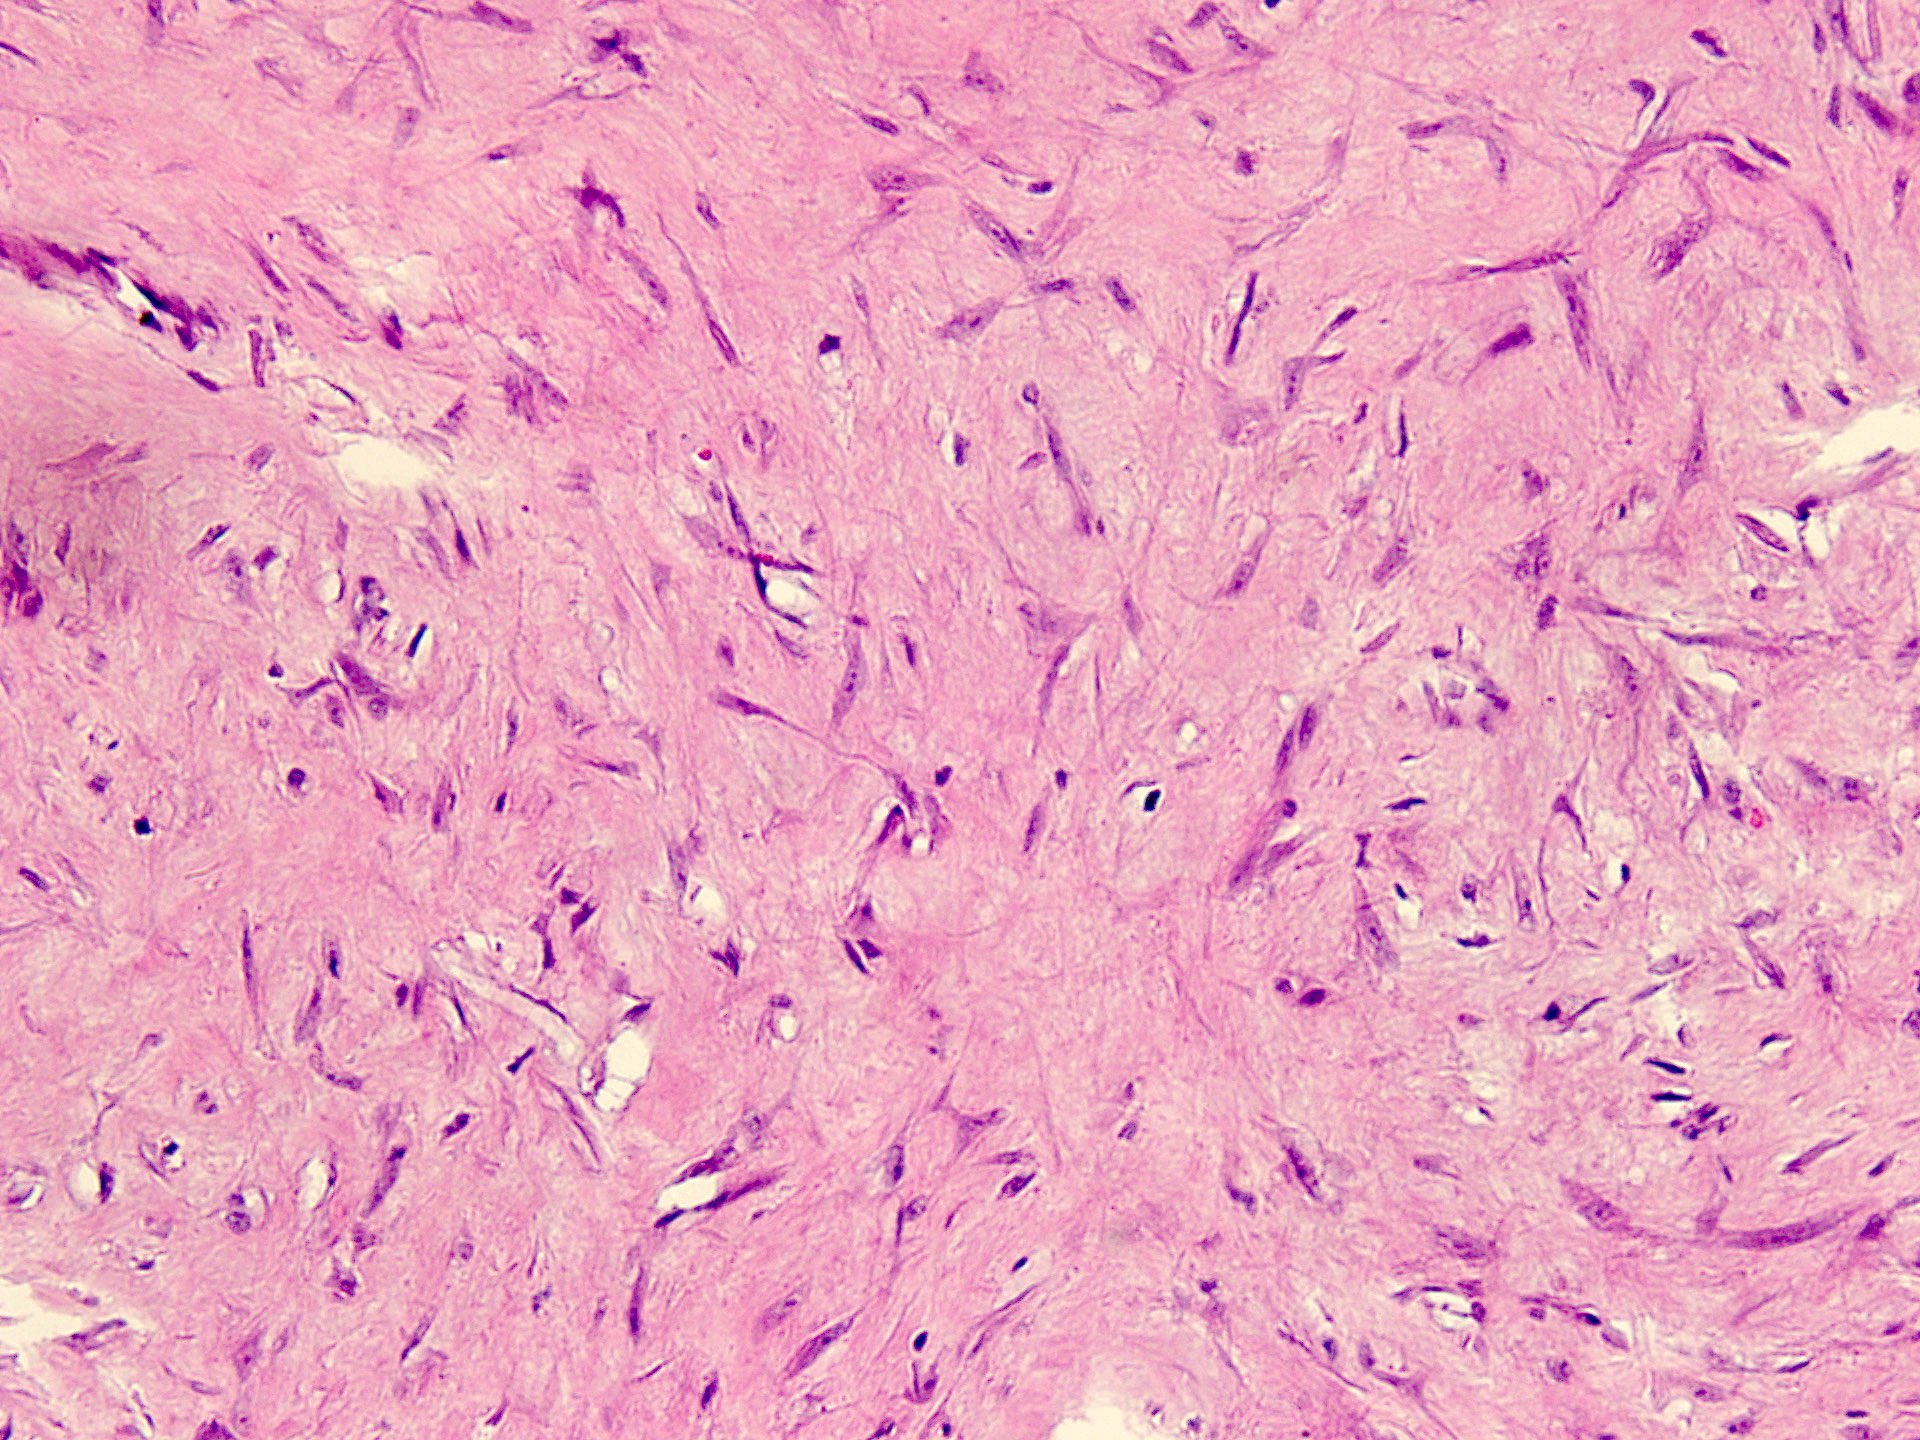

Microscopic (histologic) description

- Well circumscribed tumor of variable cellularity

- Cellularity mostly higher at tumor edges

- Bland spindle cells in a collagenous background

- Tumor has characteristic thin walled slit-like vessels

- Degenerative changes like myxoid / cystic change, osseous / chondroid metaplasia can be seen

- Bizarre pleomorphic cells can also be present

- Mitotically inactive

- Necrosis not present

- Cellular variant of fibroma of tendon sheath also exists; it overlaps morphologically with nodular fasciitis and fibrous histiocytoma (Cancer 1979;44:1945)

Microscopic (histologic) images

Contributed by Nasir Ud Din, M.B.B.S.

- Comment: Histology showed a well circumscribed, variably cellular lesion composed of bland spindle cells having regular nuclei arranged in sheets and fascicles. Thin walled vessels are present. The background is collagenous.

A 32 year old man has had painless swelling in the palm of his hand for 6 months. It was excised and the histology is shown in the above image. What is the most likely diagnosis?